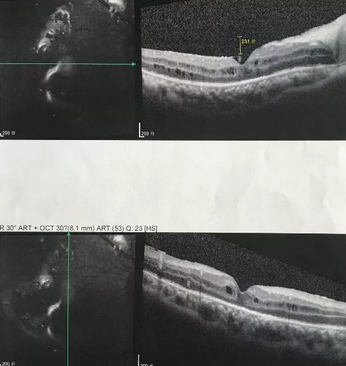

独眼,视网膜全脱离已成窄漏斗状、陈旧性葡萄膜炎、瞳孔后黏连无法散大,且并发白内障使得视网膜周边部细节情况无法看清,左眼已无光感,角膜白斑,瞳孔闭锁,还填充着硅油。右眼既往葡萄膜炎病因不清,一年中发病3、4 次都是用激素医治。左眼多年前是“天那水”溅入后又发生玻璃体出血手术后……令人担心的是这次我们克服重重困难救治全部脱离的视网膜 后,可能会面对长期慢性葡萄膜炎、长期药物医治的继发性高眼压,以及葡萄膜炎的再次复发等,稍有不慎就是不逆性致盲了。